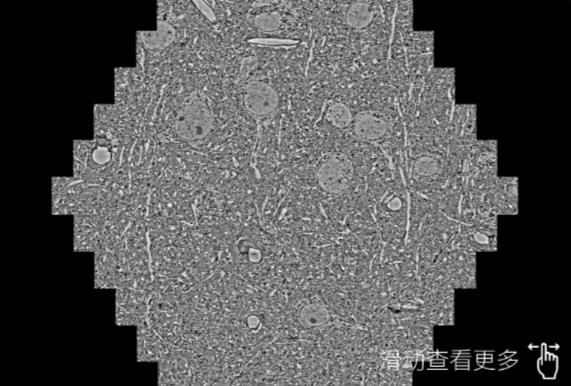

鼠脑切片。左图使用十堰蔡司十堰扫描电镜MultiSEM706对165μmx143pm面积区域成像,耗时仅需1.5秒。右图为鼠脑切片中30μm区域放大效果。样品由芝加哥大学B.Kasthuri提供。

使用蔡司高速十堰扫描电镜MultiSEM对1mm²人脑皮层组织进行高分辨成像,并对其中的各种细胞结构进行三维重构分析。左图展示了2x3mm²组织平面中锥体神经元的三维重构效果。右图显示了局部体积神经元三维重构。图像由哈佛大学chtman实验室提供,渲染图由D. Berger 制作。